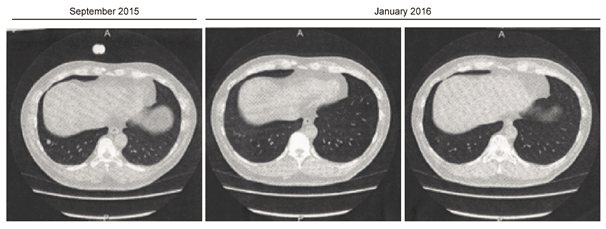

11. First case

We applied this treatment on a recurred patient (48 years old male) who suffered from the recurrence of Leiomyosarcoma as pathological diagnosis on the upper right hand. After surgical resection (27, May, 2015), the sarcoma metastasized to the lung in September, 2015. Chemotherapy was performed with doxorubisin (126mg), but it did not disappear by December, 2015. Therefore, the patient presented at my hospital, and he subsequently received the cancer re-differentiation-inducing treatment (Figure 36). Left photograph shows a CT at September, 2015, center and right photograph show the CT at January, 2016. As shown in CT image, metastases have clearly disappeared after January 2016 (Table 1). The patient’s initial risk assessment according to the TMCA was classified as tumor stage V (=G2), whereas, in July 2017, the TMCA risk assessment was classified as TS (III). There is no relapse of recurrence for 2 years after he received re-differentiation inducing treatment.

Figure 36 CT finding of case 1 after resection of sarcoma on left upper-hand, sarcoma was metastasized to the lung. But metastasis was disappeared one month after the re-differentiation inducing treatment.